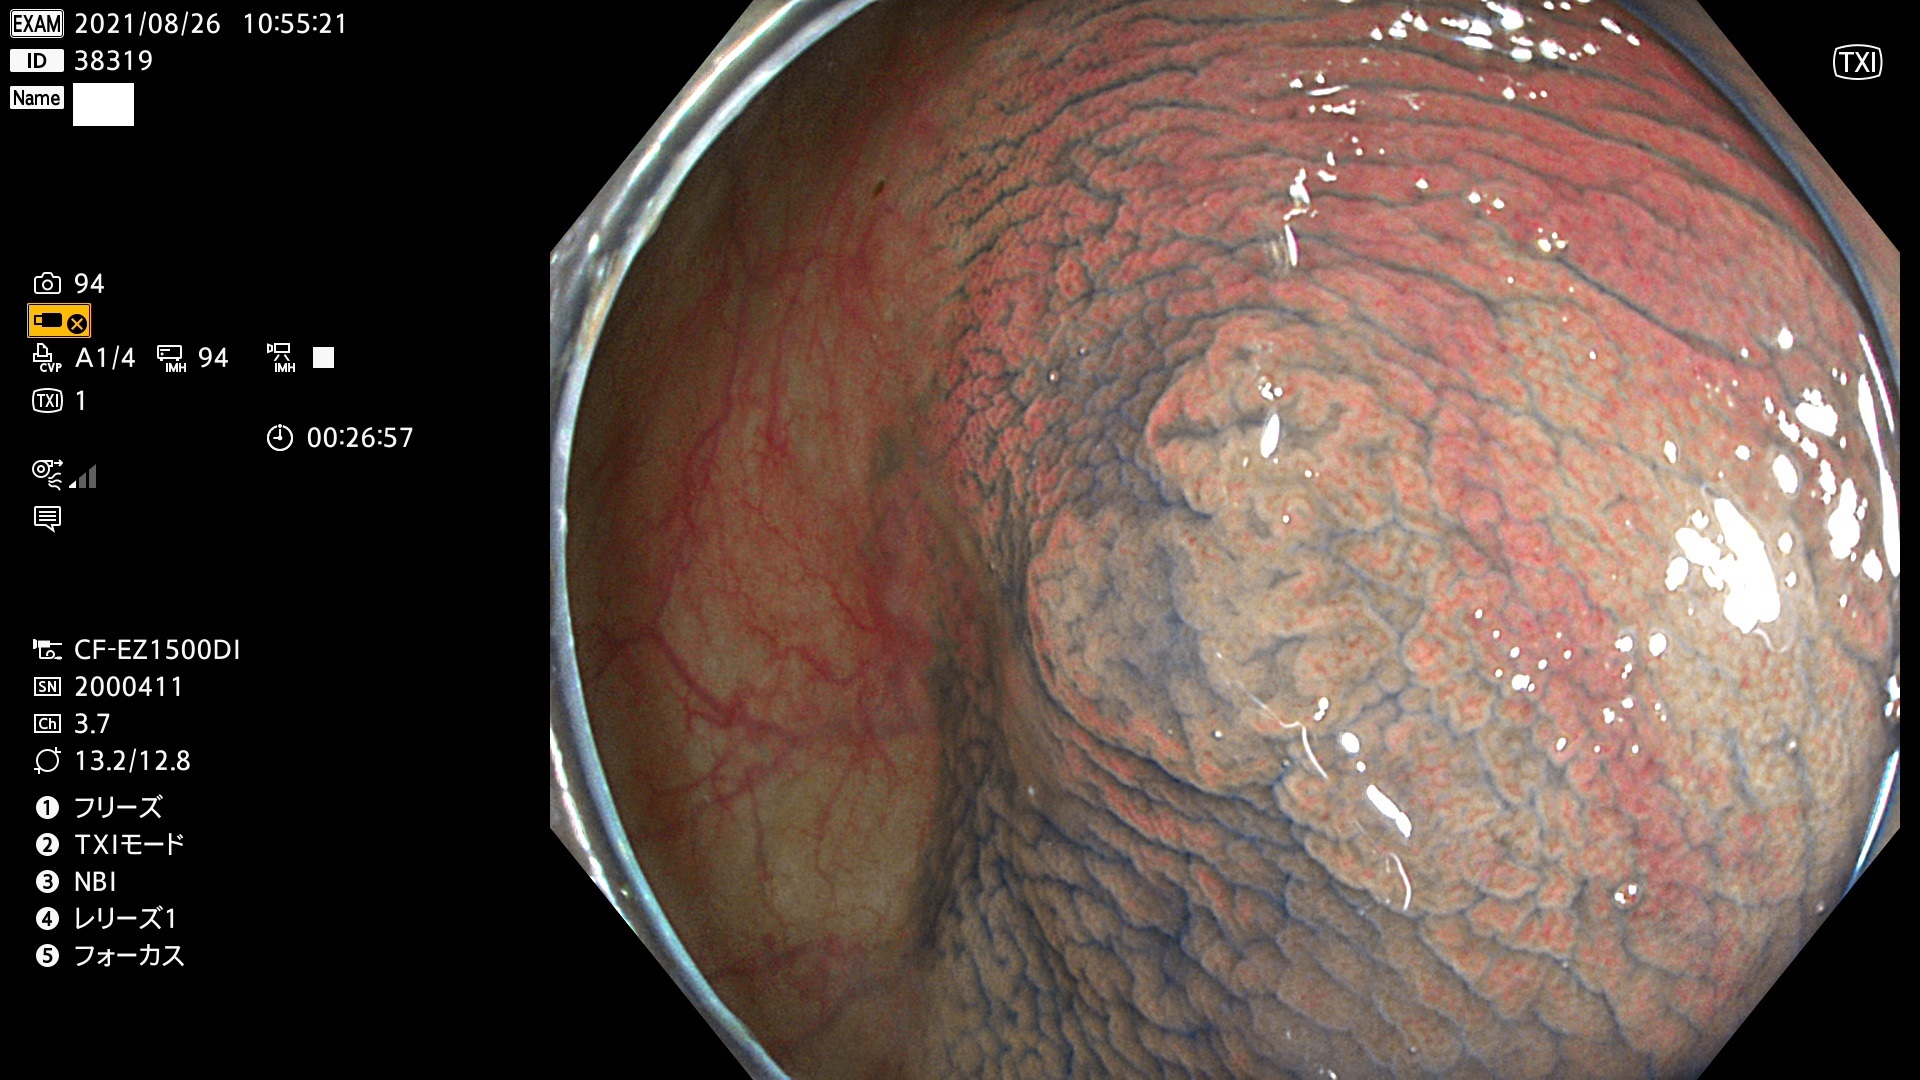

38300 38301 38302 38303 38304 38306 38307 38308 38309 38310 38311 38312 38313 38314 38315 38316 38317 38319 38321 38322 38323 38324 38325 38327 38331 38332 38333 38334 38337 38338 38339 38340 38341 38343 38346 38348 38349 38350 38351 38352 38353 38354 38355 38358 38359 38360 38361 38362 38363 38365 38366(SSAP) 38368 38369 38370 38371(SSAP) 38372 38374 38375 38376 38377 38378 38380 38381 38382 38383 38384 38385 38386 38388 38389 38391(SSAP) 38395 38397 38399

発見困難で危険性の高い平坦型病変(上記100名より抽出)